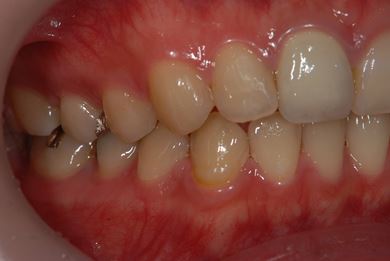

| 性別/年齢 | 女性 / 21歳 | ||||||||||||||||||||||||||||||||

| 主訴 | 現在、金属の入っている歯が虫歯になっているようなので、治してセラミックにしたい。 | ||||||||||||||||||||||||||||||||

| 治療方針 | セラミック治療にて審美的回復を行う。 | ||||||||||||||||||||||||||||||||

| 治療内容 | ハイブリッドセラミックインレー6本 | ||||||||||||||||||||||||||||||||

| 総治療費 | 189,000円 | ||||||||||||||||||||||||||||||||

| 治療期間 | 3ヶ月 |